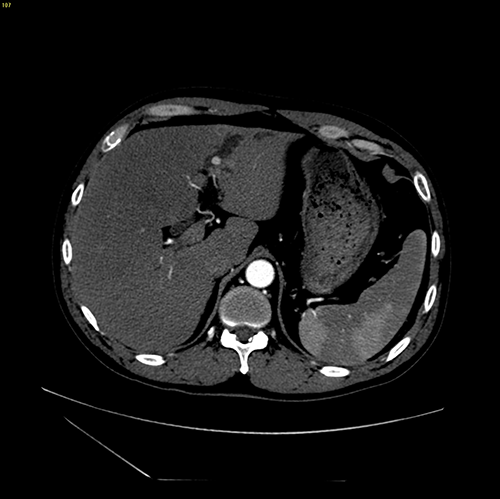

左肝胆管结石--腹腔镜左肝叶切除